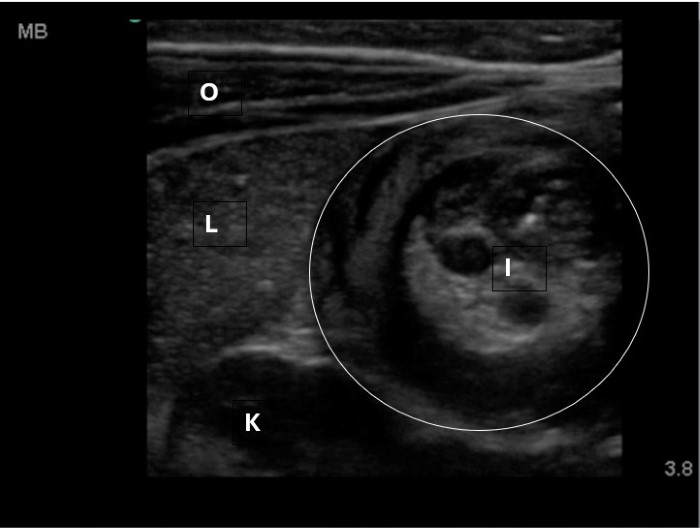

The linear probe is placed in the RLQ in the transverse position with indicator to the patient’s right. Identify the psoas muscle and iliac vessels lying medial. Once these structures are visualized, slide lateral and look superficially to identify the cecum. (Figures 1a,1b 1) Use graded compression-progressive increase and decrease of pressure to move any gas out of view. Keeping the lateral edge of the abdominal cavity in view (Figure 2), the ultrasound probe should slide cranial in traverse plane, visualizing the ascending colon until the hepatic flexure.  In this location, the colon turns just medial to the liver with the kidney deep in the view. (Figure 3) This is the most common location to identify ileocolic intussusception. If no tissue mass is identified, the probe should be turned to the sagittal plane with indicator toward the head (to keep the colon visualized in the transverse view) and moved across the transverse colon continuing to use graded compression to look for a tissue mass consistent with intussusception. Once at the splenic flexure (Figure 4), the probe should be transitioned back to the transverse orientation to interrogate the descending colon.

10-2024 Article7-1a.pngFigure 1a. Unlabeled anatomy of identifying landmarks of RLQ to identify cecum.

10-2024 Article7-1b.jpgFigure 1b. Right lower quadrant anatomy: A-iliac artery, B-iliac vein, P-psoas muscle, C-cecum of identifying landmarks of RLQ to identify cecum.